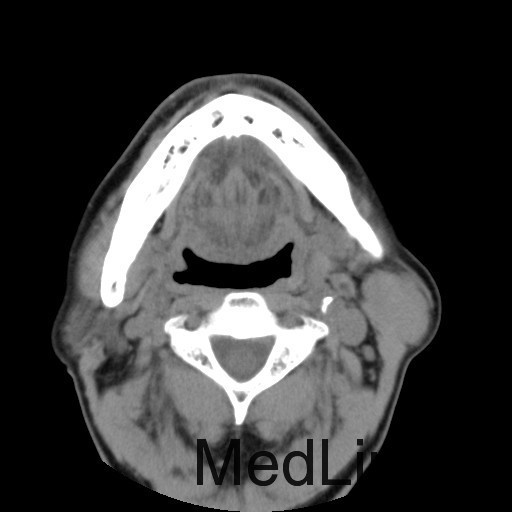

患者:男,64岁。 主诉:左耳垂下肿物1年余 病史:患者1年余前发现左耳垂下肿物,逐渐增大,与进食无关,无疼痛、麻木感,未予治疗。 体查:左右颜面部基本对称,双侧上、下颌骨未及明显异常膨隆,左耳垂下腮腺区见一膨隆肿物,大小约为4cm×3cm,边界欠清,质软,表面皮肤无红肿、破溃、出血,无触痛,皮温正常,活动度可。 辅助检查:无

诊断:左腮腺肿物(?) 治疗:入院后上颌CT平扫+增强:左侧腮腺深叶结节灶,考虑良性病变,腺淋巴瘤与多形性腺瘤鉴别,排除手术禁忌症,于2015-10-16送手术室全麻下行"左腮腺深叶肿物切除+面神经解剖+邻近皮瓣转移修复术"。术后病理提示:左腮腺肿物,符合多形性腺瘤。